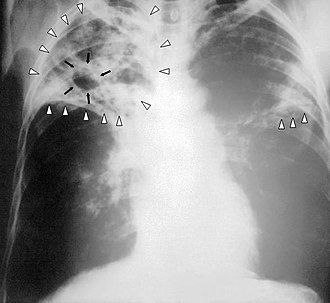

✔️Sil kasalligining belgilari ✔️Yo’tal. (Dastlab quruq, ammo tayoqchalar tarqalishi bilan namga aylanadi. U kamida 3 hafta davom etadi.) ✔️Past darajadagi isitma (normadan 1-2 daraja yuqori). ✔️Qonli yo’tal. ✔️Ko’krak qafasidagi og’riq. ✔️Qattiq terlash (ayniqsa kechasi). ✔️Jismoniy mashqlar paytida nafas qisilishi. ✔️Zaiflik,…